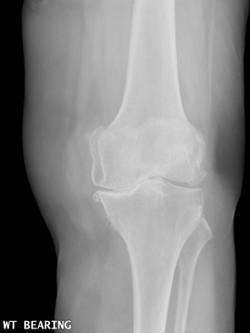

| Osteoarthritic Knee |

Normal Knee |

The cartilage is a padding that absorbs stress. Usually the pain early on is due to inflammation. In the later stages, when the cartilage is worn away, most of the pain comes from the mechanical friction of raw bones rubbing on to each other.